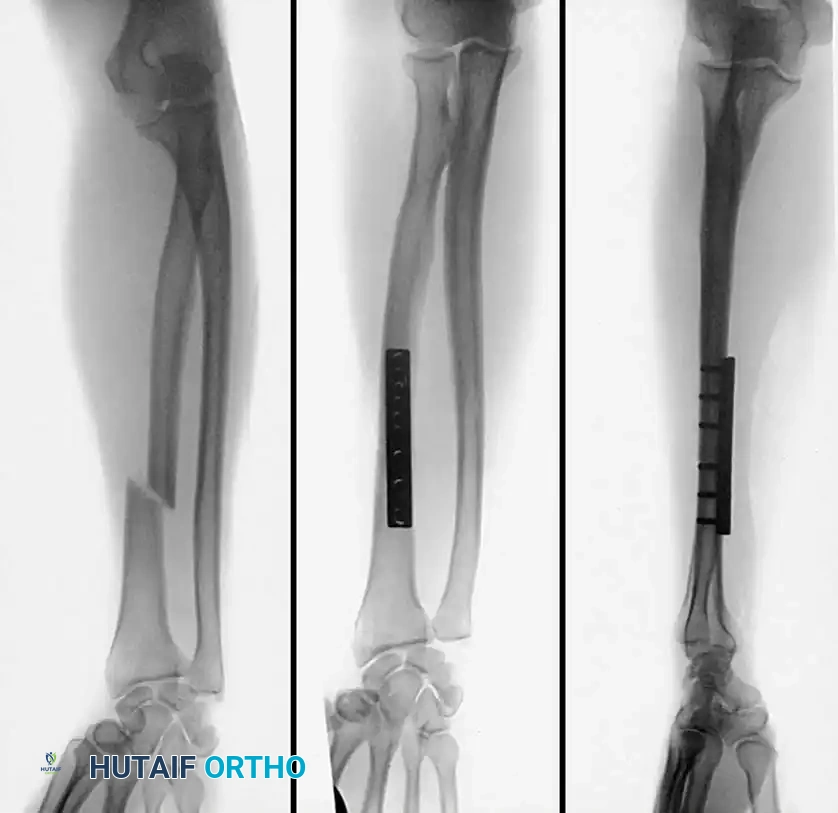

4. Plate Osteosynthesis

If comminution with bone loss prevents the use of a tension band compression technique—due to the risk of shortening the olecranon and narrowing the greater sigmoid notch—plate fixation is mandatory. Plating is also the gold standard for Monteggia fracture-dislocations, oblique fractures extending distally, and fractures involving the coronoid process.

Construct Design:

Hand-contoured reconstruction plates or modern, anatomically precontoured locking plates (e.g., Acumed, Synthes) provide rigid, stable fixation. The plate is applied to the posterior (tension) surface of the ulna.

Fig. 54-58 A-C, Plate fixation can be used to stabilize comminuted fractures of the olecranon. Precontoured plates offer excellent proximal purchase with locking screws. (From Heim U, Pfeiffer KM: Internal fixation of small fractures, 3rd ed, Berlin, 1988, Springer-Verlag.)

🔪 Surgical Technique: Plate Fixation

- Reduction: Restore the articular block. Temporary K-wires can be used to hold comminuted articular fragments.

- Plate Application: Apply a precontoured olecranon plate to the posterior aspect of the proximal ulna. The proximal portion of the plate often wraps over the tip of the olecranon to capture the proximal fragment with multiple locking screws.

- Fixation: Secure the plate distally to the ulnar shaft using standard cortical or locking screws. If an oblique fracture line is present, a lag screw can be placed independently or through the plate to achieve interfragmentary compression.

- Bone Grafting: If significant metaphyseal void exists after elevating impacted articular fragments, autogenous cancellous bone graft or allograft should be packed into the defect prior to final plate tightening.